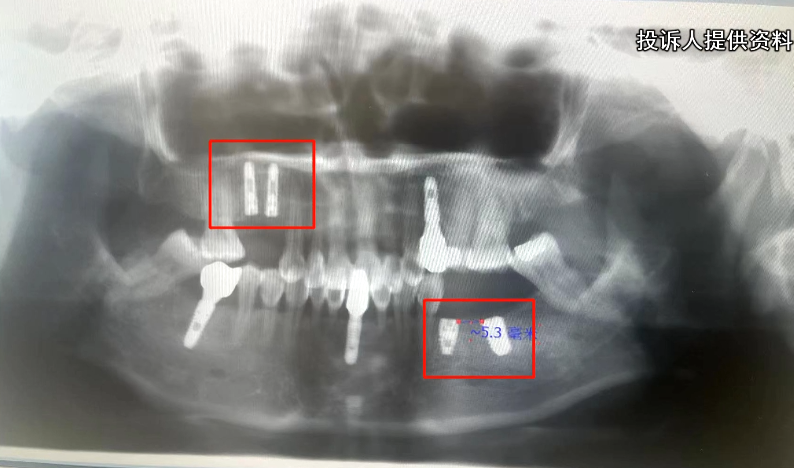

吴女士反映,她是2022年7月,在美奥口腔完成4颗牙齿的种植,总共花费了20000元。

然而,牙齿种植完之后她发现,种植进去的,其实是韩国产的奥齿泰。

在这份聊天记录中我们看到,吴女士多次提到自己要种植的是美国的品牌,但是在最终的收款单上,却清楚的写着奥齿泰,两个品牌的种植体,目前的差价在1000元左右。